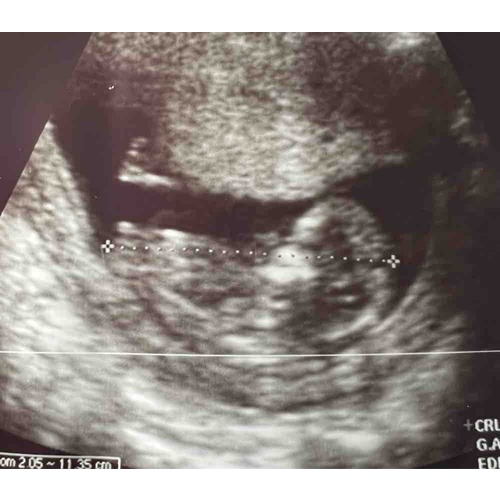

Goedemorgen, gisteren echo gehad bij 12+0; enig idee? Ik kan er niks van maken zelf..

En de andere echo

Goedemorgen, gisteren echo gehad bij 12+0; enig idee? Ik kan er niks van ma ...

Voor nu 💗 maar niet overtuigd De nub is nog in ontwikkeling Krijg je nog een 13w echo?